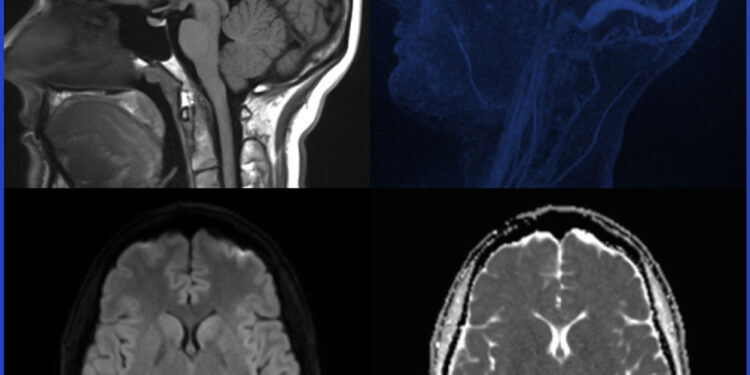

- Vaizdiniai tyrimai, dažniausiai magnetinio rezonanso tomografija (MRT), leidžianti įvertinti nervų sistemos mielino kiekį.